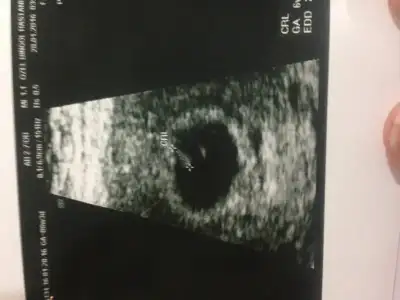

Havalianne__ Havalianne__ bana da bi yorum yaparmısın rica etsem:) çok ortada senin yorumunu merak ediyorum.. Burda 9 haftalık ve karından çekildi

Eklentiler

• image.webp

image.webp

17,5 KB · Görüntüleme: 140